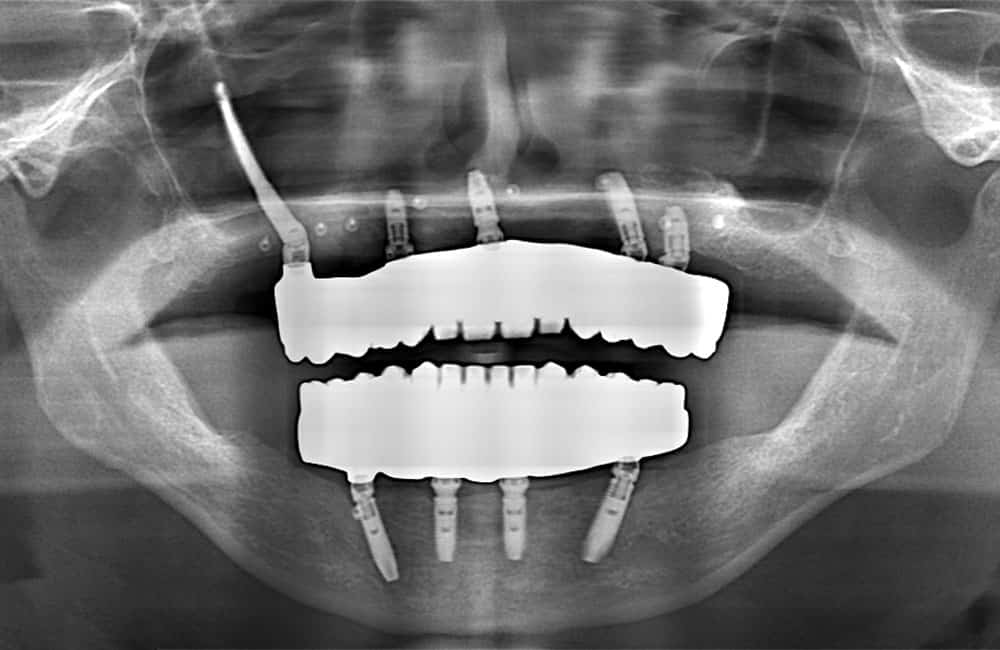

他院でザイゴマインプラント治療を受けた後、仮歯の噛み合わせが悪いため噛みづらく顔貌も変わってしまった。また頬に違和感を感じたため当院を受診。

術前のパノラマX線画像

左右のザイゴマインプラントが頬骨から大きく飛び出し頬を触ると違和感がある -

術後のパノラマX線画像

前方のインプラントは残し、他院埋入のザイゴマインプラントを除去し、同時に新しいザイゴマインプラントを適切な位置に再埋入を行っております。治療後数年経過しておりますが良好な状態を保っております。